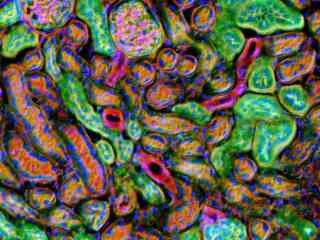

Fluorescence Microscopy

The widefield reflected light fluorescence microscope has been a fundamental tool for the examination of fluorescently labeled cells and tissues since the introduction of the dichromatic mirror in the late 1940s. Furthermore, advances in synthetic fluorophore design coupled to the vast array of commercially available primary and secondary antibodies have provided the biologist with a powerful arsenal in which to probe the minute structural details of living organisms with this technique. In the late twentieth century, the discovery and directed mutagenesis of fluorescent proteins added to the cadre of tools and created an avenue for scientists to probe the dynamics of living cells in culture. This gallery examines the fluorescence microscopy of both cells and tissues with a wide spectrum of fluorescent probes.

Rat Sections

The humble rat has had an outsized impact on human history. In the Middle Ages, the black rat (Rattus rattus) was blamed for spreading the Black Plague through its fleas, a pandemic that killed a third of Europe's population, an estimated 34 million people. In modern times, however, a larger cousin, the Brown rat (Rattus norvegicus) has become an important model organism in biological research. Selective breeding of the Brown Rat has produced the albino laboratory rat. Rats grow quickly to sexual maturity and are easy to keep and breed in captivity.